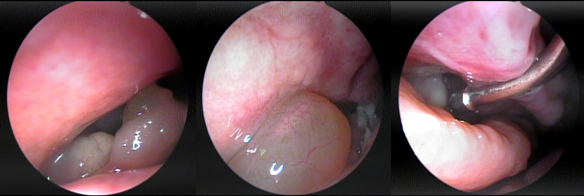

Polyp mũi bên trái Polyp mũi bên phải

Polip hốc mũi phải

Bn ĐTM - 61 tuổi

Bn NPT - 41 tuổi

Polyp mũi là một trong những biến chứng của bệnh viêm mũi xoang mạn tính, là một bệnh lý có dạng u phát triển trên bề mặt niêm mạc của các cấu trúc bên trong hốc mũi như cuốn giữa (Middle Turbinate), khe mũi giữa (Middle Meatus), hoặc cửa lỗ xoang hàm, xoang sàng hoặc trong lòng các xoang. Về mặt giải phẫu Polyp thường xuất hiện cả hai bên hốc mũi, có nhiều múi, có thể quan sát được khi nội soi, có màu hồng nhạt, hoặc hơi xám, bóng nhắn, mềm và có thể di động lắc nhẹ khi có tác động của một lực tiếp xúc. Vị trí hay gặp nhất là Polyps ở khe giữa, có thể phát triển kích cỡ lấp đầy khe này và lan rộng bít kín hốc mũi; Polyp có thể triển ra phía sau che kín lỗ mũi sau và thõng xuống vòm họng.

Cắt Polyp mũi: Thường gặp là polyp phát sinh từ mặt bên cuốn giữa (Lateral side of middle turbinate) bít kín khe mũi giữa (Middle Meatus). Một tỷ lệ rất nhỏ là những polyp nằm ở khe trên che kín đường dẫn lưu các xoang sau.

Kỹ thuật: Minimally Invasive Sinus Technique (MIST): Kỹ thuật này có ưu điểm lớn là duy trì được chức năng sinh lý giải phẫu mũi xoang. MIST chỉ cắt khối polyp đang làm dầy cộm mặt bên cuốn giữa, có thể cắt thêm một phần lưỡi liềm của mỏm móc để mở thông thoáng khe giữa, làm rộng thống đường dẫn đến các lo tự nhiên của xoang hàm. trán, sàng trước. MIST được thực hiện đơn giản và an toàn.